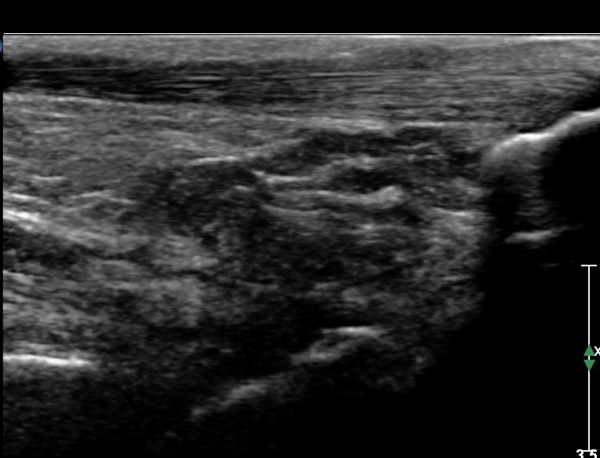

ÃÊÀ½ÆÄ °Ë»ç :  ¹ß¸ñ ¾ÕÂÊ Á¾´Ü¸é°Ë»ç¿¡¼­ ƯÀÌ ¼Ò°ß º¸ÀÌÁö ¾Ê´Â´Ù(»çÁø 1)

Àü°ÅºñÀδë ÇϺΠÁ¾´Ü¸é°Ë»ç¿¡¼­ Àü°ÅºñÀδëÀÇ Àú¿¡ÄÚ À§Ãø°ú Á·±Ùµ¿ÀÇ ¼ö¾×Àú·ù°¡

°üÂûµÈ´Ù(»çÁø 2, 3, 4).